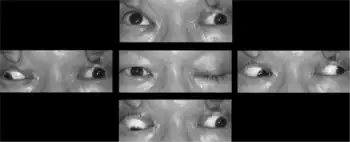

Oculomotor nerve palsy or oculomotor neuropathy[1] is an eye condition resulting from damage to the third cranial nerve or a branch thereof. As the name suggests, the oculomotor nerve supplies the majority of the muscles controlling eye movements (four of the six extraocular muscles, excluding only the lateral rectus and superior oblique). Damage to this nerve will result in an inability to move the eye normally. The nerve also supplies the upper eyelid muscle (levator palpebrae superioris) and is accompanied by parasympathetic fibers innervating the muscles responsible for pupil constriction (sphincter pupillae). The limitations of eye movement resulting from the condition are generally so severe that patients are often unable to maintain normal eye alignment when gazing straight ahead, leading to strabismus and, as a consequence, double vision (diplopia).

Signs and symptoms

A complete oculomotor nerve palsy will result in a characteristic displacement outward (exotropia) and downward (hypotropia). The outward displacement occurs because the lateral rectus muscle (innervated by the sixth cranial nerve) maintains muscle tone in comparison to the paralyzed medial rectus. The downward displacement occurs because the superior oblique muscle (innervated by the fourth cranial or trochlear nerve) is unantagonized by the paralyzed superior rectus, inferior rectus and inferior oblique. The affected individual will also have a ptosis, or drooping of the eyelid, and mydriasis (pupil dilation).